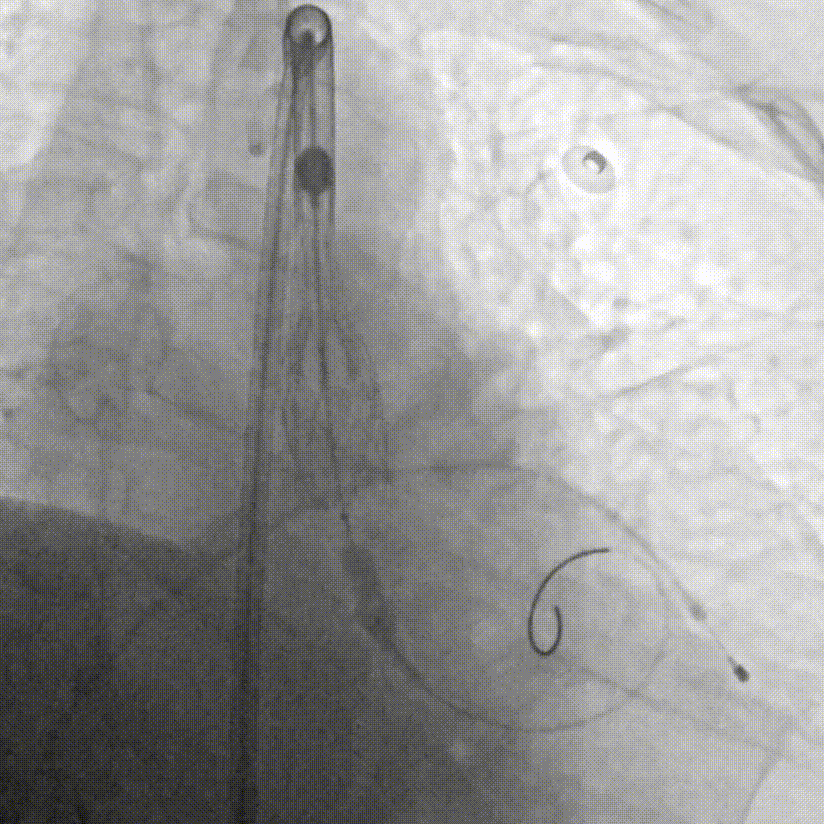

手术当日,在多学科团队的紧密监控与配合下,首先由心脏重症监护科蓝新平主任团队顺利建立VA-ECMO(图C),为患者筑起了坚实的“生命之桥”。随后,钟炜教授手术团队在影像学的精准引导下,凭借娴熟技术及团队默契配合,通过血管路径将人工瓣膜输送至心脏预定位置,一次精准释放,即刻解除了“心门”的梗阻(图D--G)。整个手术过程中,ECMO运行平稳,患者生命体征始终保持稳定,未出现预期中的血流动力学剧烈波动及消化道出血加重的情况,顺利完成手术操作。

D.成功跨瓣后行球囊扩张

E.行主动脉根部造影,精准定位

F.缓慢、平稳、逐步释放瓣膜支架

G.瓣膜支架成功释放